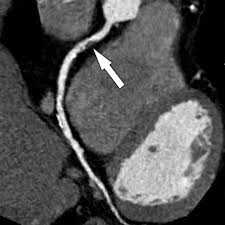

Стрелками обозначены участки сужения почечных артерий, выявленные на КТ

В нашем центре применяется неионный контраст, который отличается хорошей переносимостью и редким возникновением аллергических реакций. Препарат полностью выводится из организма в течение суток и не оказывает негативного воздействия на здоровье пациента.